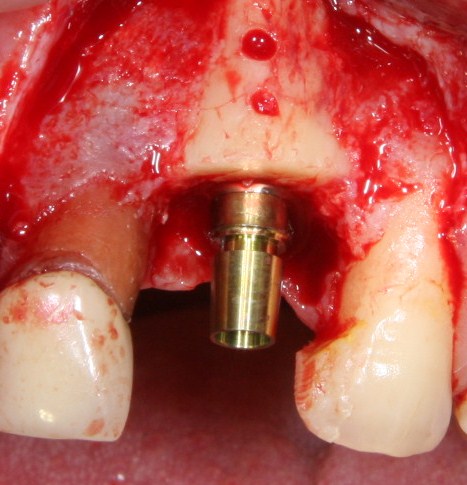

Установка имплантатов

По ряду уже упомянутых выше причин, для решения этой клинической задачи мы выбрали имплантаты Xive. Лунки для них мы уже приготовили. возможную первичную стабильность оценили. Имплантаты мы установили с усилием чуть больше 15-20 Нсм — такого крутящего момента более, чем достаточно, особенно если учесть, что временные коронки будут соединяться между собой.

Подробно о том, что такое крутящий момент и хирургический протокол можно прочитать здесь>> и тут>>, соответственно. Из-за использования специальных индивидуализируемых временных абатментов, имеющих только три положения, нам нужно позиционировать платформу имплантатов по граням. Это очень просто  — мы выводим вырез абатмента TempBase (он входит в комплект поставки) вестибулярно.

После перкуторной проверки стабильности имплантатов и точности позиционирования, мы переходим к следующему этапу — сохранению десневого контура.

Установка имплантатов занимает около двух минут.